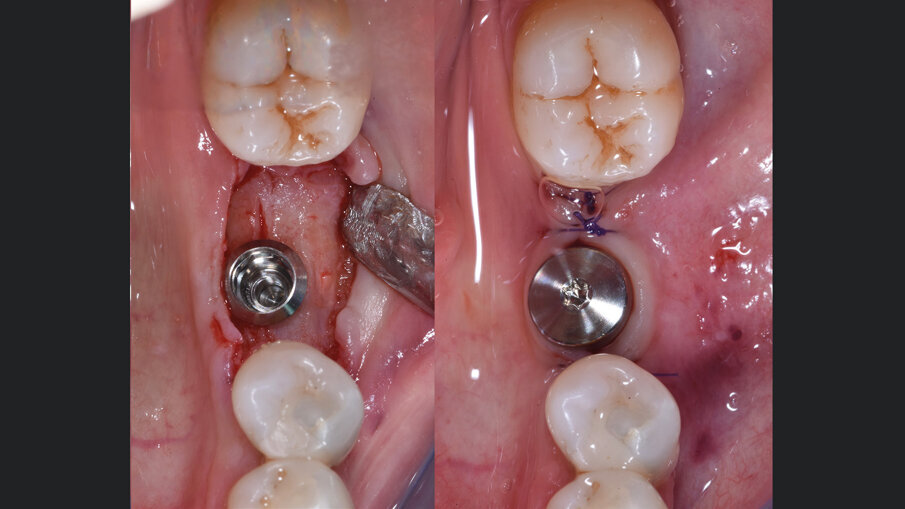

Gli innesti eterologhi utilizzati, ottenuti mediante un processo di deantigenazione enzimatica (Zymo-Teck, Bioteck) sono caratterizzati dalla presenza della componente minerale inalterata e del collagene osseo in conformazione nativa. Grazie a queste proprietà, l’innesto viene riconosciuto fisiologicamente da osteoclasti ed osteoblasti3 e viene rimodellato con osso del paziente in tempi fisiologici4, 5. Inoltre, la lamina corticale di origine equina, subisce un ulteriore trattamento di parziale demineralizzazione, che espone il collagene preservato e ne permette la caratteristica flessibilità che la rende facilmente adattabile alle diverse geometrie della cresta alveolare6, 7. Veniva quindi inserito un impianto (Straumann Tissue Level 4,5 x 8,5 mm), l’ISQ di 79 suggeriva la simultanea inserzione della vite di guarigione e tre mesi più tardi veniva consegnata la protesi definitiva in zirconia (Figg. 6-8). A 24 mesi dalla consegna della protesi, veniva eseguita una RX di controllo che mostrava un ottimo mantenimento volumetrico dell’osso alveolare (Fig. 9).

Fig. 6 - A sinistra, inserimento dell’impianto a 6 mesi dalla GBR (inserito con 50 N/cm). A destra, chiusura dei lembi e vite di guarigione per favorire la guarigione dei tessuti in vista della consegna della protesi.